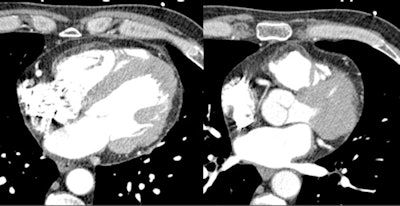

Dilated cardiomyopathies are often characterized by enlarged ventricular cavities, with thinning of the myocardium down to < 1 cm. If CT images in systole are available, it's also worth looking at the mitral valve, which may show the nonapposition of the mitral valve leaflets as a sign of dilated cardiomyopathy and dilation of the myocardial valve ring.

"Of course, the real purpose of looking at cardiomyopathy with CT is not to study the myocardium but rather the coronary arteries -- and this is a pretty easy task because these patients tend to have low ejection fractions and the hearts beat very slowly, so the images tend to be of very good quality," Becker said.

Also, CT has proved useful for distinguishing ischemic from idiopathic cardiomyopathy, and CT can be as accurate as cardiac catheterization in distinguishing patients with idiopathic cardiomyopathies, just based on visualization of the coronary arteries, he explained. Thus, ischemic cardiomyopathy cases were distinguished by extensive coronary disease.

In one case Becker showed, acute myocardial infarction was characterized by low attenuation indicating lack of contrast uptake or edema, while chronic myocardial infarction manifested as myocardial thinning.